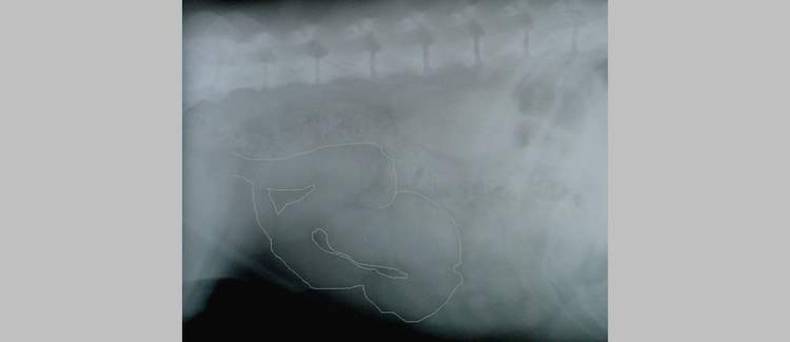

Bron foto:Kalumet, Milchleistentumor Hund Resektionsprinzipien, CC BY-SA 4.0